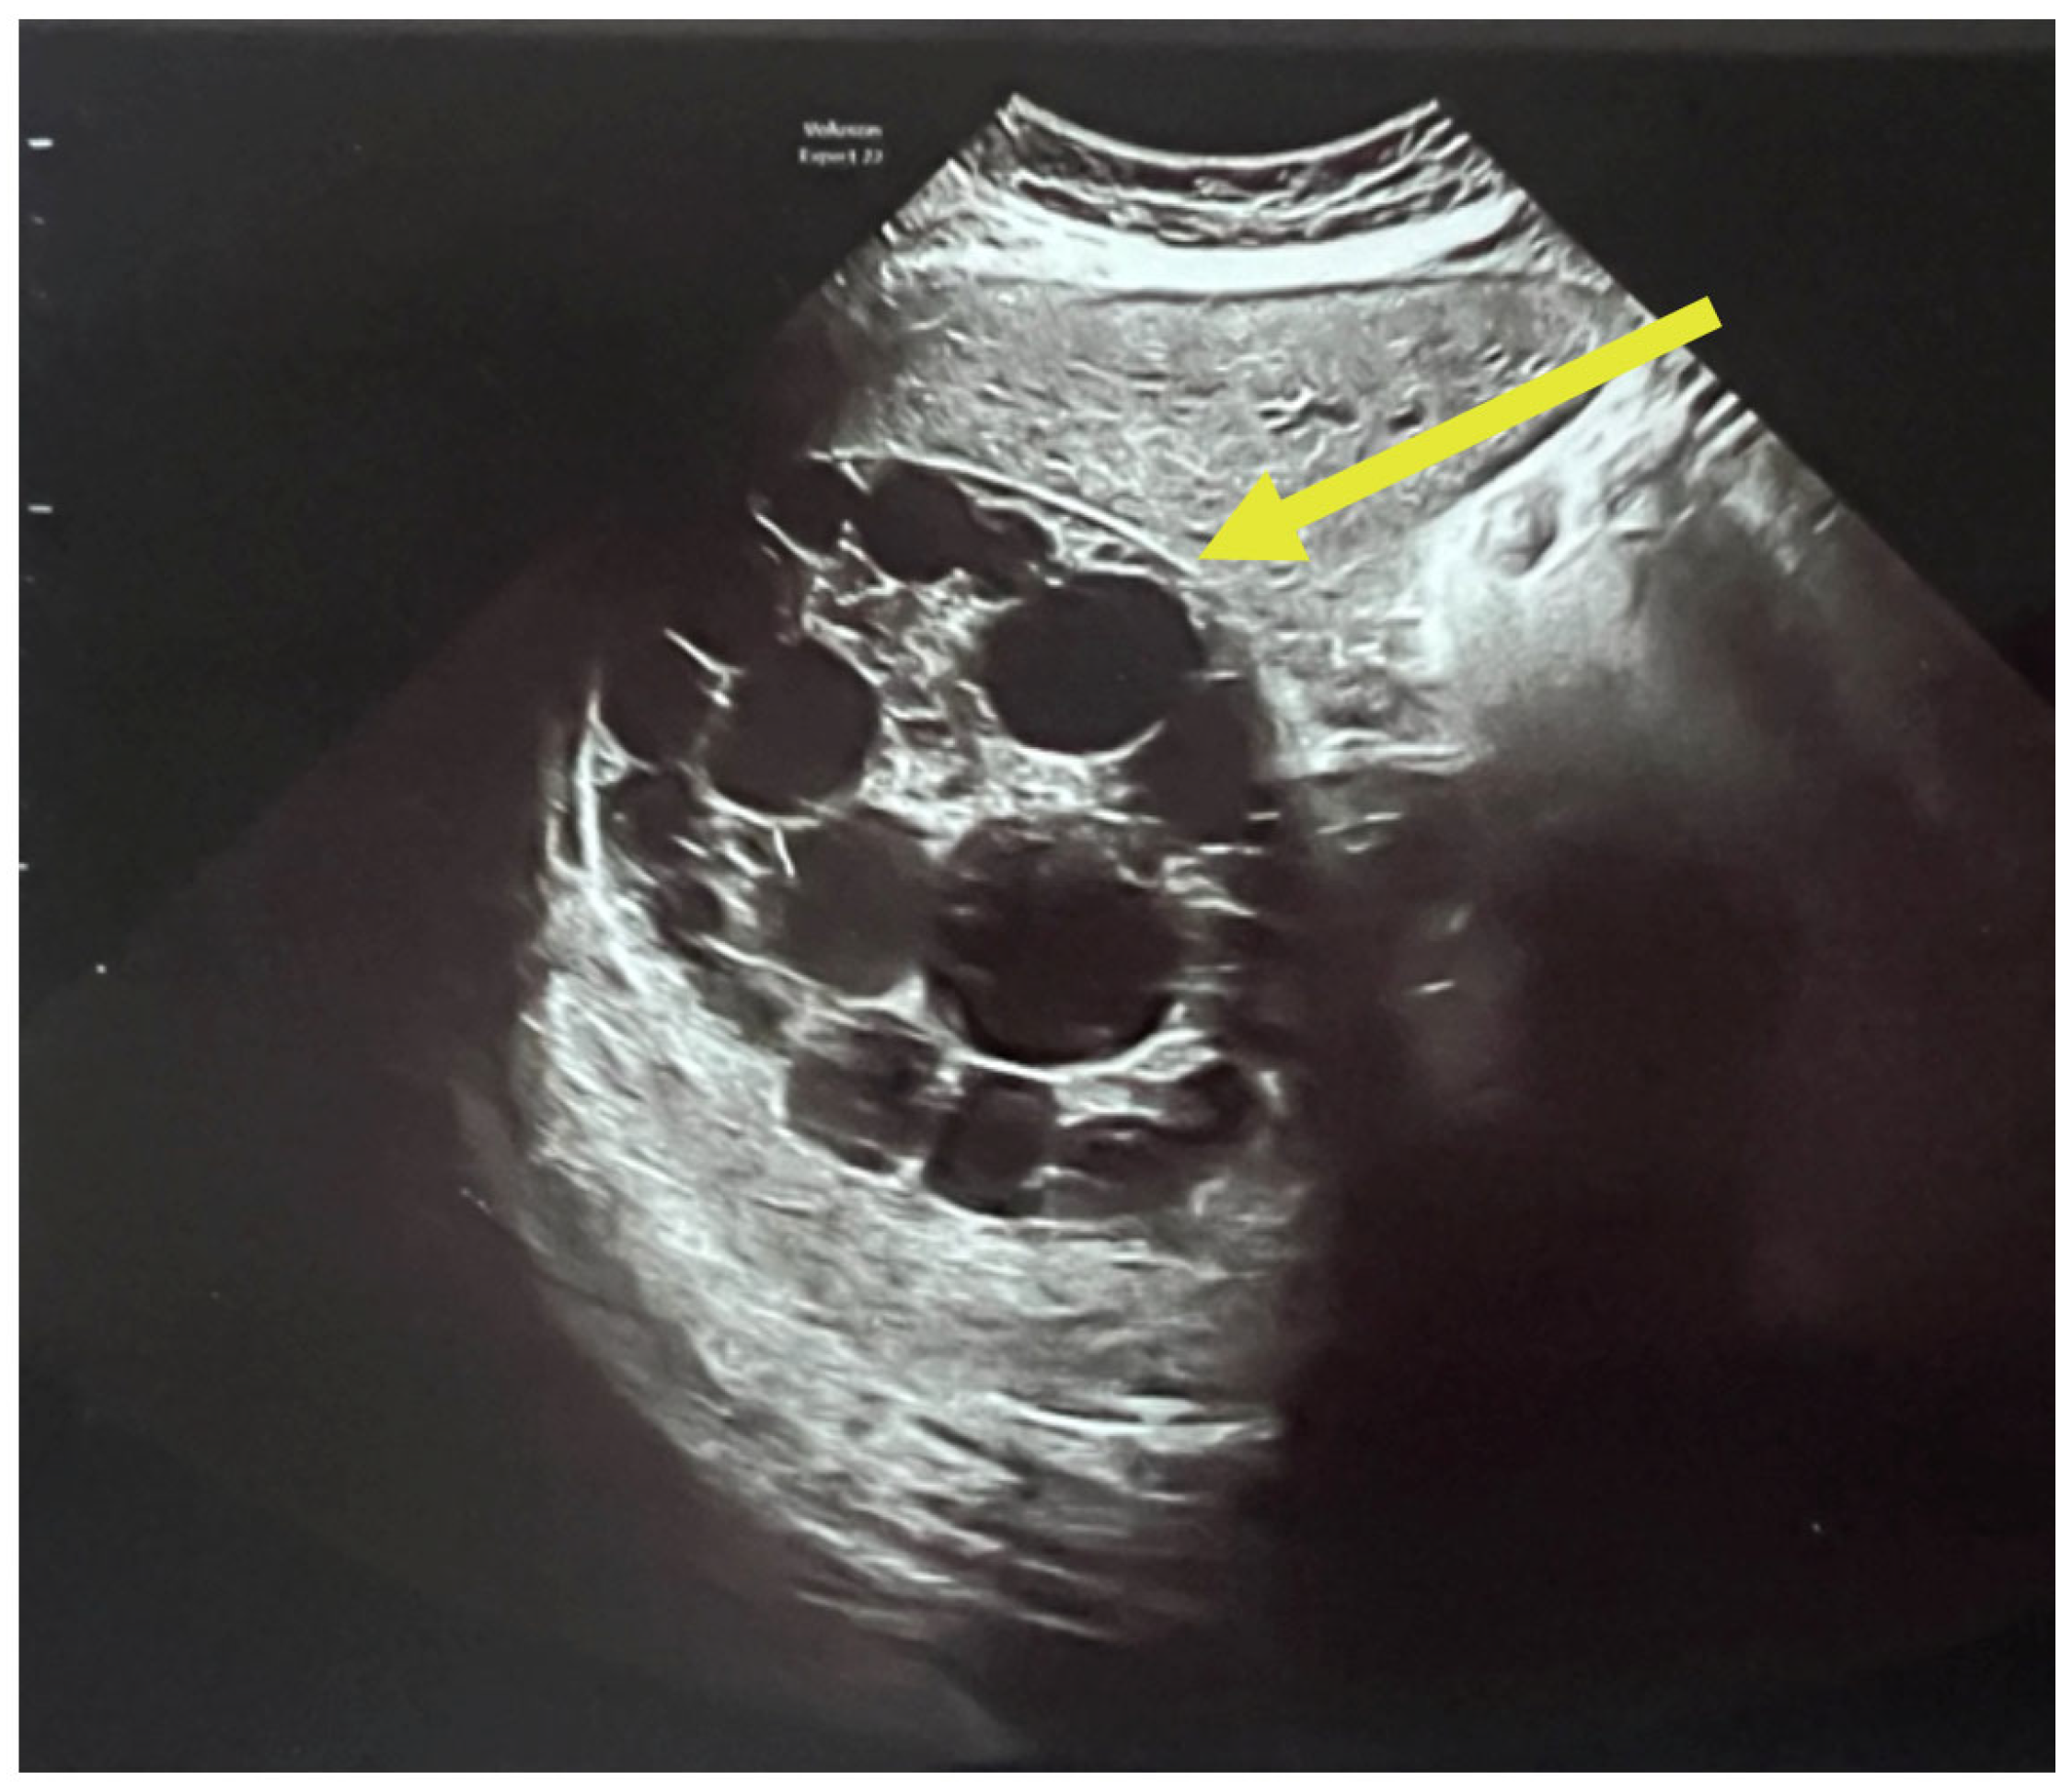

A complete abdominal examination showed an enlarged abdomen due to the gravid uterus, movement upon respiration, slight upper abdominal quadrant pain and no peritoneal irritation. The infectious disease consultation proposed an echinococcal etiology based on cyst features and recommended serological tests for Echinococcus granulosus IgM and IgG and an abdominal and pelvic MRI. As it can be seen in Figure 3, the patient had two large hepatic hydatid cysts: a 12 × 9 cm type 2 cyst (with daughter vesicles) in the right lobe and an 8.5 × 8 cm type 4 cyst (pseudoparenchymatous) in the left lobe.

The multiplicity and defined arrangement of daughter cysts within the mother cyst reflect a high risk for spontaneous or traumatic rupture, especially concerning during pregnancy, due to the potential for anaphylaxis, secondary echinococcosis and disseminated disease. Figure 4 below shows the internal septations and vesicles of the cyst.

Figure 3. Ultrasound of hydatid cyst with multiple daughter cysts: large, well-defined hydatid cyst with internal multiple daughter vesicles—a hallmark of Echinococcus granulosus infection. The cyst shows a “rosette” or “honeycomb” appearance, characteristic of CE2-stage cysts per WHO classification [23].

Figure 4. Ultrasound of the hydatid cyst with internal septations and vesicles: numerous daughter vesicles of varying sizes are visualized, separated by fine septations, enhancing the suspicion of active parasitic proliferation.